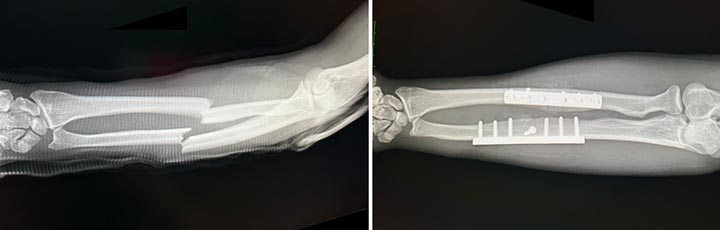

図4

図4. 大人の骨折。プレートと骨ネジで固定した。